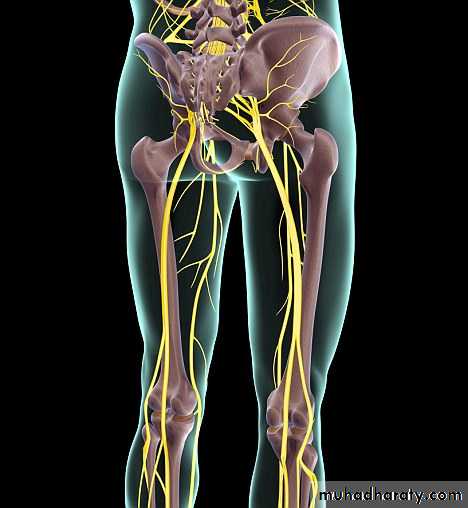

NEUROLOGICAL STATE OF LOWER LIMB

Straight leg rasing test.Muscular system.

Sensory sysytem.

Reflexes.

Cutaneous distribution of nerve roots